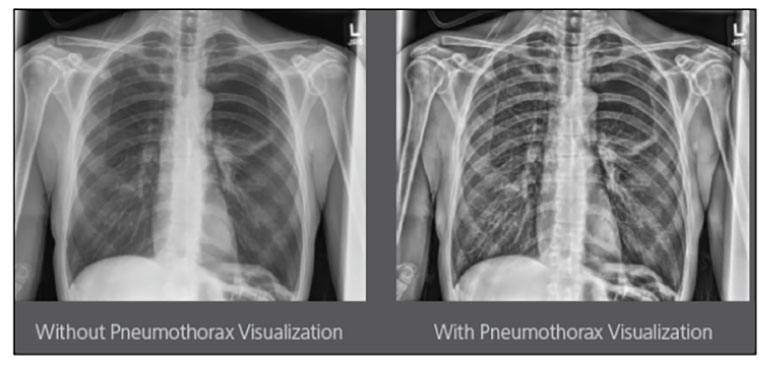

Our Carestream Focus HD 35/43 Retrofit Detectors, powered by Image Suite Software, are an ideal solution to step up to full digital X-ray for customers who simply cannot compromise on image quality. It seamlessly integrates into existing setups, bringing the power of full digital X-ray with minimal disruption and maximum clarity, along with the following benefits: